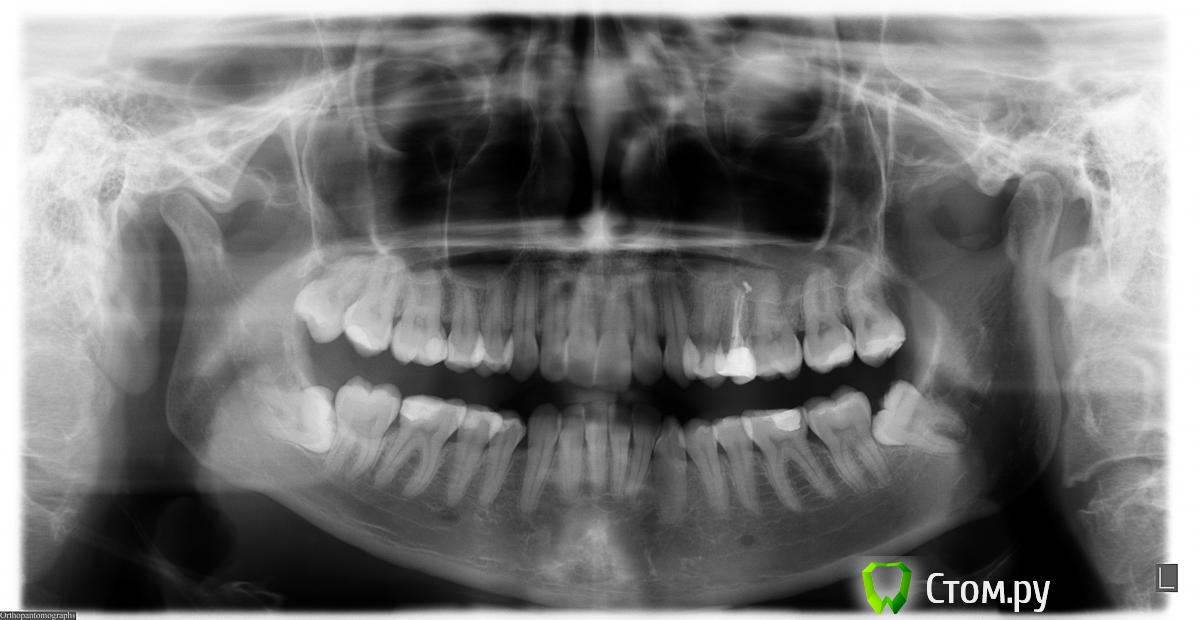

Alexandra86 Опубликовано 22 декабря, 2013 Поделиться Опубликовано 22 декабря, 2013 Доброго времени суток, уважаемые доктора.Вчера утром удалили верхнюю правую прорезавшуюся восьмерку по ортодонтическим показаниям (зуб цел, воспалений нет). После удаления хирург сообщил, что есть небольшое повреждение пазухи ("маленькая дырочка"), что чревато гайморитом, если ее не закрыть, вставил тампон с лекарством, назначил осмотр через 7 дней, и сказал, что отверстие должно затянуться. По моим наблюдениям врач рану не ушивал, никаких лоскутов не накладывал, только тампон. Также не было назначено антибиотиков (при удалении нижних восьмерок также не назначал, при этом знаю, что пациентам с более сложными вмешательствами (имплантация) назначет обязательно).Больше никаких назначений не было. Придя домой и залезши в интернет я пришла в ужас, т.к. в разных источниках пишут, что данные повреждения не зарастают самостоятельно, что нужна хирургическая операция, что в большинстве случаев после такого повреждения возникает гайморит и т.д.В связи с эти 2 вопроса:1. Нужно ли сейчас предпринимать дополнительные меры - бежать к ЛОРу, просить назначение на антибиотики, ушивать рану? На сегодняшний день (2ой день после удаления) - состояние нормальное, из носа ничего не течет, сильных болей нет, ощущается привкус лекартсва во рту периодически (чем-то напоминает йод).2. Насколько компетентны действия врача (мне нужно будет удалять последнюю верхнюю восьмерку)? Хирурга выбирала долго по рекомендациям, были идеально удалены нижние сложные ретинированные восьмерки, без осложнений, очень доверяла ему и шла спокойно на удаление верхних и получила такой сюрприз. В некоторых источниках пишут, что такие осложнения связаны только с анатомическими особенностями, в других - с плохой квалификацией врача. Также по-разному описывают действия врача в таких ситуациях - например что рану нужно обязательно ушить, что в моем случае сделано не было.Помогите, пожалуйста, разобраться.Снимок приложен. Спасибо заранее. Ссылка на комментарий

kriokov Опубликовано 22 декабря, 2013 Поделиться Опубликовано 22 декабря, 2013 1. По Вашему описанию, нет оснований для дополнительных мероприятий, посетите своего врача , когда он Вас назначил, 2. В обл удаленных верхних 8, точечные незначительные перфорации , как у Вас, заживают и самостоятельно. 3. У Вас перфорация связана с анатомией, так не было большой дырки в гайморову, и прочих проблем. Ссылка на комментарий

red_butler Опубликовано 22 декабря, 2013 Поделиться Опубликовано 22 декабря, 2013 В вашей ситуации были анатомические предпосылки для пенетрации пазухи. Теперь диспансерно наблюдать, в случае формирования сообщения - пластика Ссылка на комментарий